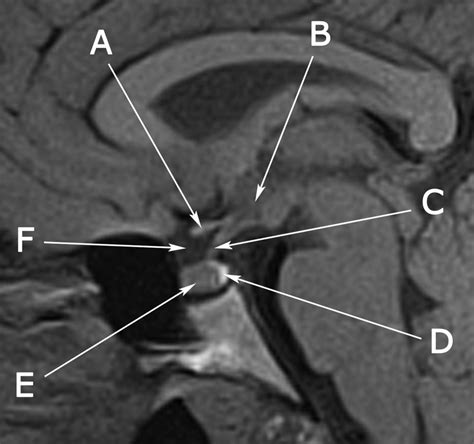

A Pituitary Gland MRI is a non-invasive imaging technique that uses magnetic fields and radio waves to produce detailed images of the pituitary gland and surrounding structures. This imaging modality is particularly useful for detecting abnormalities, tumors, and other conditions that may affect the pituitary gland. The MRI provides high-resolution images that allow healthcare professionals to make accurate diagnoses and develop appropriate treatment plans.

Interpreting the results of a Pituitary Gland MRI involves analyzing the images to identify any abnormalities, tumors, or other conditions that may affect the pituitary gland. Healthcare professionals look for:

• Structural Abnormalities: Structural abnormalities, such as pituitary cysts or congenital anomalies, can also be identified on a Pituitary Gland MRI.